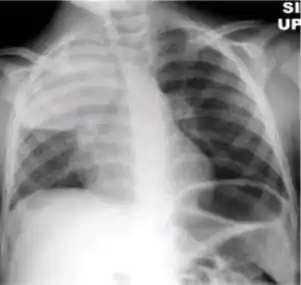

Dense homogenous opacity in right, middle and lower lobe of primary pulmonary TB.